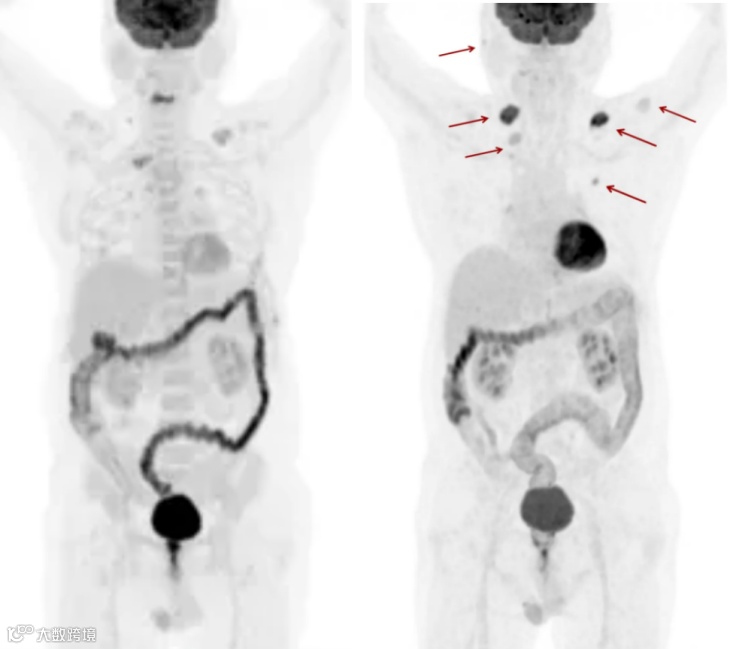

老年男性,CT发现肺癌1周,拟行手术治疗。做PET/CT进行术前分期,发现右侧胸膜种植转移,避免了不必要的手术治疗。